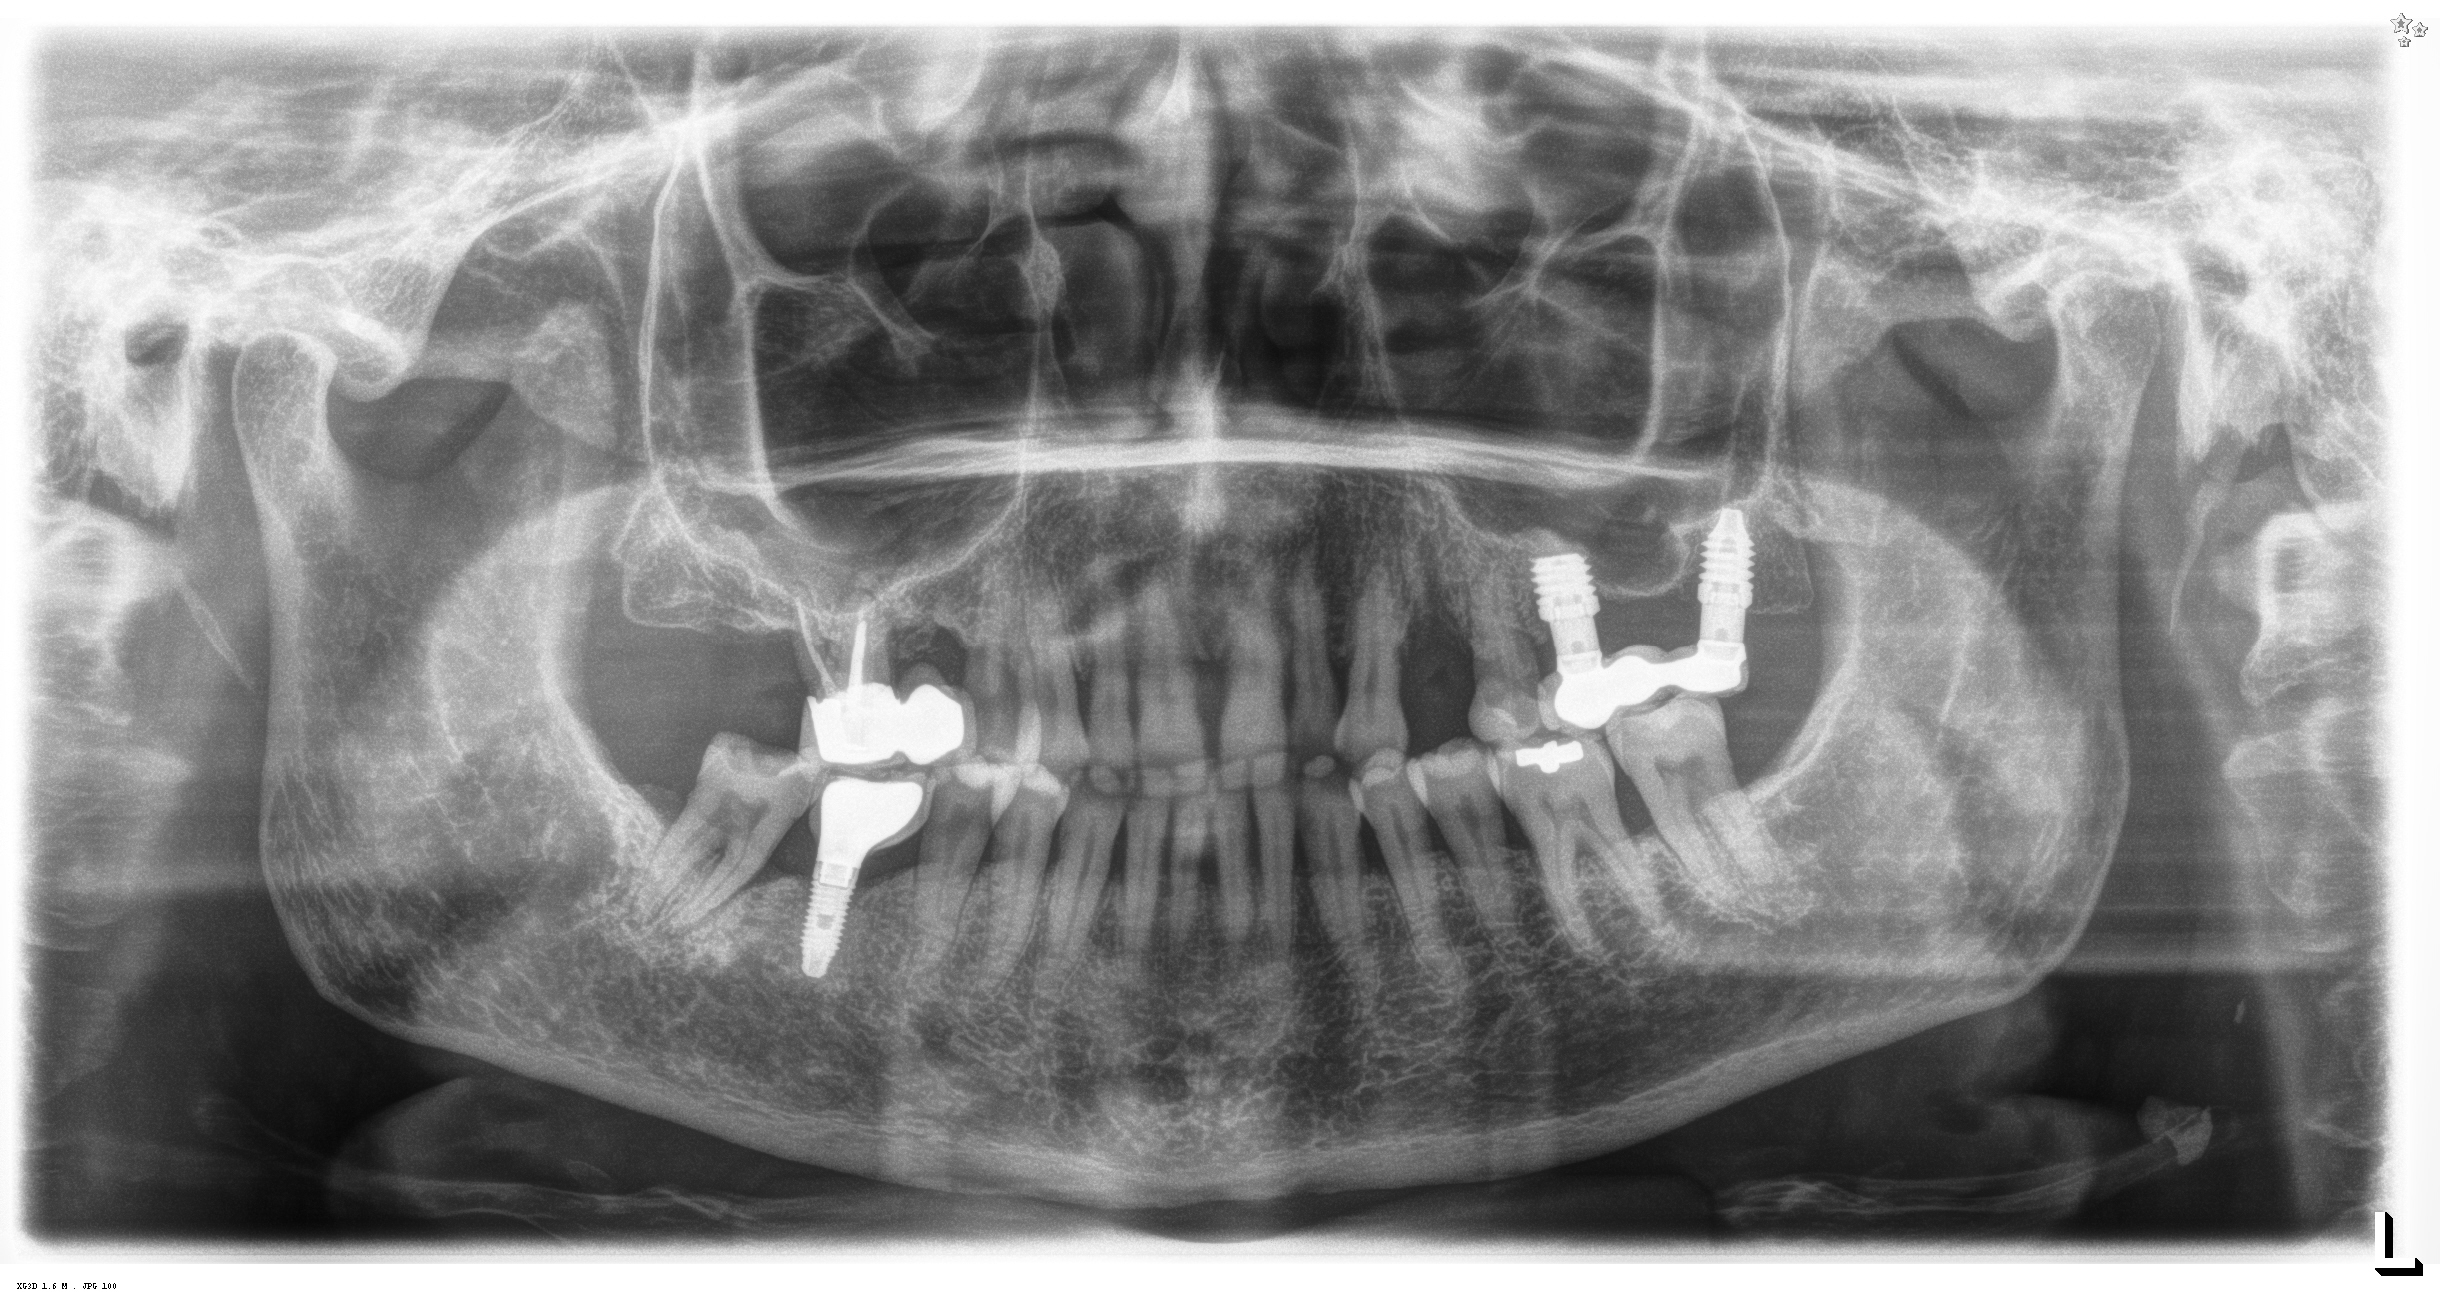

Le OPT a posizionamento del paziente standardizzato sono state eseguite alla consegna della protesi (3 mesi per la mandibola, 6 mesi per la maxilla) e a 1,3, 6 e 12 mesi dopo il carico. Le radiografie sono state calibrate con ImageJ utilizzando l’impianto di lunghezza conosciuta per correggere la magnificazione, mentre la perdita d’osso marginale è stata misurata dalla spalla dell’impianto al primo punto di contatto tra osso e impianto. Il dato principale è la perdita di osso marginale mesiale e distale; i dati secondari sono invece la sopravvivenza degli impianti e le complicazioni chirurgiche/protesiche. Il test di Shapiro-Wilk verifica la normalità; le variabili qualitative sono riassunte in base alla frequenza, mentre le variabili quantitative in base a media e deviazione standard. La sopravvivenza è analizzata con lo stimatore di Kaplan-Meier utilizzando il software SPSS v15.0 (Statistical Package for Social Science versione 15.0).

Il 20% degli impianti è stato posizionato nella mandibola (per lo più in posizione 47) e il restante 80% nel mascellare superiore (il 20% in posizione 16 e il 20% in posizione 25). Gli impianti posizionati nel mascellare superiore hanno trovato un osso tipo IV, mentre gli impianti posizionati nella mandibola hanno trovato un osso tipo III. Gli impianti utilizzati hanno un diametro compreso tra 4.0 e 4,5 mm (il 66.7% sono da 4.0 mm) e una lunghezza compresa tra 4.5 mm e 7.5 mm (il 53.3% sono lunghi 7.5 mm). Nell’86.7% dei casi non è stato eseguito alcun procedimento chirurgico aggiuntivo; in un caso, due impianti hanno previsto in rialzo di seno transcrestale con PRGF-Endoret e osso autologo. Nel 93.3% dei casi la protesizzazione ha previsto ponti avvitati a più elementi; un impianto è stato protesizzato mediante elemento singolo avvitato con componente transepiteliale. Il follow-up medio è stato di 12.4 ± 1.05 mesi dal carico. Il 100% degli impianti è sopravvissuto, senza complicanze né chirurgiche né protesiche. La perdita di osso media a 12 mesi è stata mesialmente di 0.15 ± 0.74 mm e distalmente di 0.13 ± 0.85 mm. La Figura 4 mostra l’osso perso su un singolo impianto e le Figure 5-14 illustrano un caso clinico rappresentativo.